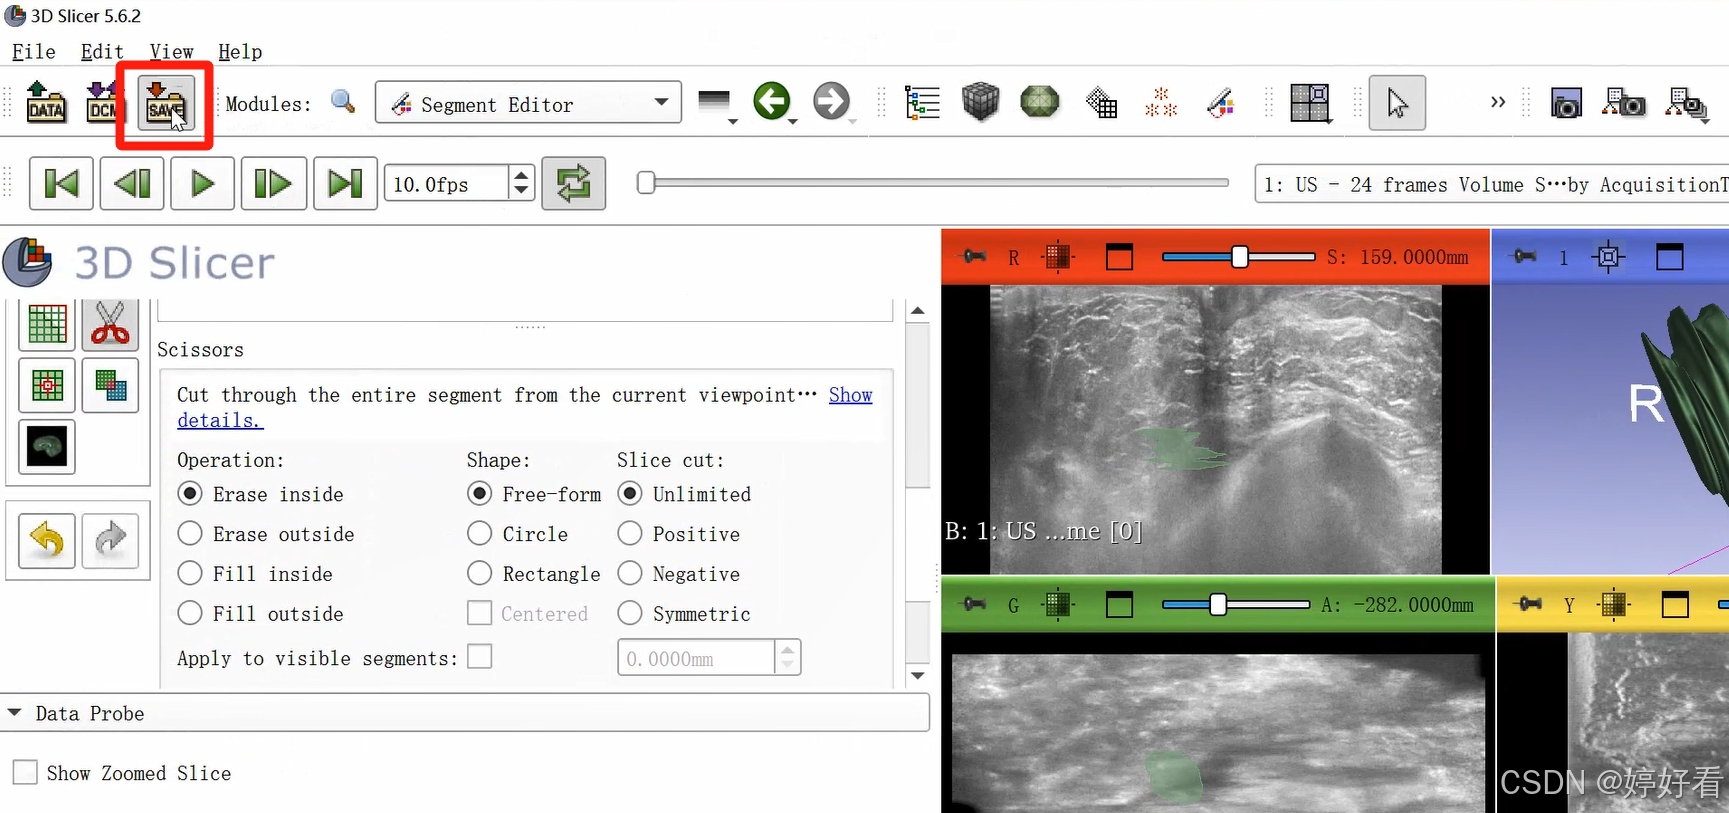

2.8 剪刀功能

剪刀功能的选项较多。以第一个Erase inside功能为例,也就是把圈起来部分里面的内容减掉。